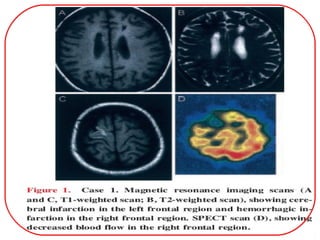

CT scan: infarction may involve cortical and subcortical

regions. In the patients with parenchymal hemorrhage

CT usually show a high density area indicating blood in

the basal ganglia, thalamus and/or ventricular system

CBF imaging techniques for moyamoya patients

include PET, xenon CT and SPECT.

 Regional CBF in patients with moyamoya is

characteristically diminished in the frontal and

temporal lobes and and in central brain structures

that are involved with basal moyamoya vessels but

elevated in the posterior circulation territory

(cerebellum and occipital lobes).